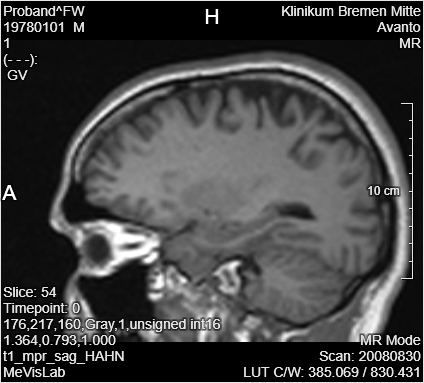

Add a LocalImage module to your workspace and select the file MRI_Head.dcm. For PyTorch, it is necessary to resample the data to a defined size. Add a Resample3D module to the LocalImage and open the panel. Change

You can use the Output Inspector to see the changes on the images after applying the resample and a swap or flip.